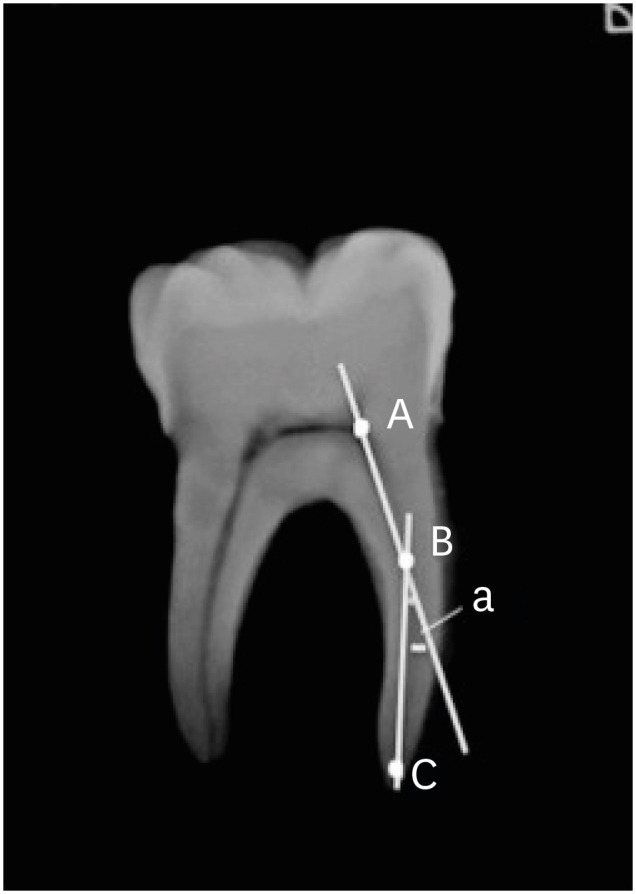

In total, 80 mature and intact mandibular first molar teeth extracted for periodontal reasons and having no caries were used. The teeth were all stored in physiological saline solution until use. All the teeth were checked using a stereomicroscope (Olympus BX43; Olympus Co., Tokyo, Japan) under ×20 magnification to determine whether there were any root fractures, cracks, or fusion in the mesial and distal roots. Periapical radiographs of each tooth were taken from the mesiodistal and buccolingual angles, digitized, and stored. The root canal curvature was determined based on the angle of curvature starting at the coronal aspect of the apical third of the root using Schneider's method (Figure 1) [15,16]. Only roots with an angle of curvature ranging between 10° and 20° were selected. Teeth with 2 canals in the mesial root and a single canal in the distal root and with similar mesiodistal and buccolingual dimensions of the pulp chamber were selected for inclusion in the study. Teeth with a root canal treatment history, internal or external root resorption, or pulpal calcification were excluded. The crown-to-apical length of the teeth was measured using a digital caliper (Digimess, São Paulo, Brazil), and teeth with similar length (20 ± 1 mm) were chosen in order to ensure standardization. All residual soft and hard tissue on the teeth were mechanically removed.

Figure 1

Diagrammatic representation of Schneider's method.

Figure 1 Diagrammatic representation of Schneider's method.